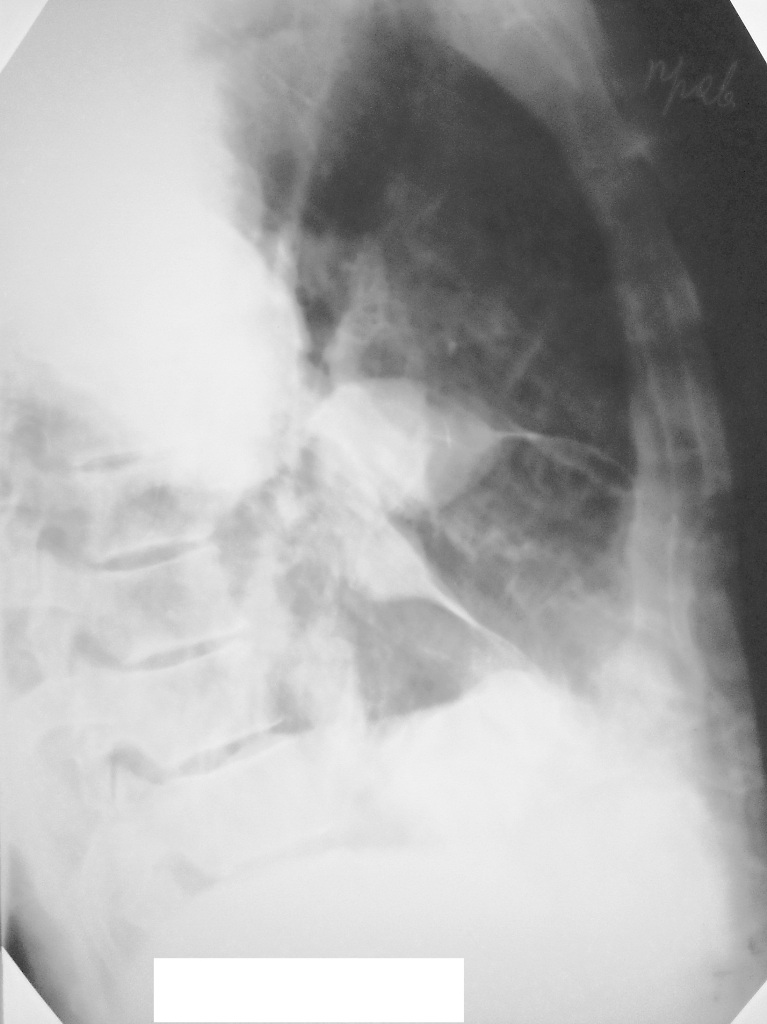

Мужчина 54 года. Слабость и лихорадка неделю. 3 недели назад спленэктомия по поводу тупой травмы живота. Поступает через несколько дней после выписки по "скорой". Дежурит пульмонолог, видит обзорный снимок, берет на бронхоскопию: данных за центральный рак нет.

Возможно пневмония, но думаю, что можно обойтись описательной картиной. Судя по всему больной стоял, так может доснять правый бок?

возможно, с  междолевым выпотом. О генезе пневмонии надо решать с терапевтом. После операции может быть, что угодно. Боковой обязателен. С уважением Nik

Добавила боковой.

За качество извиняюсь.

При поступлении 6.12. дежурным хирургом назначен обзорный снимок ОГК. После которого назначена консультация терапевта. После ФБС пульмонолог назначил боковой снимок. Утром 7.12. описывала оба снимка. Помимо междолевого выпота, не понравилась какая-то странная пневмония в нижней доле. Решила перестраховаться и взять на КТ. Реконструкции (лежа на спине):